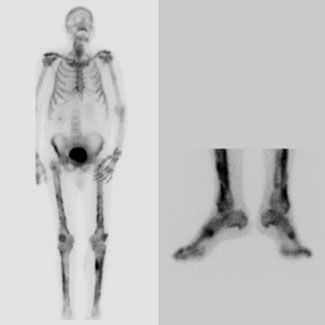

What is causing this patient’s nonresolving pneumonia and arthralgias? The patient underwent bone scintigraphy, which showed no metastatic disease but irregular uptake in both tibias and fibulas with evidence of arthritis in major joints (Figure 3). This led to the diagnosis of hypertrophic pulmonary osteoarthropathy (HPOA).

Radionuclide scanning is more sensitive than radiography in the detection of HPOA. Findings on a radionuclide scan can range from an increased “bracelet-like” appearance to more diffuse, symmetrically increased uptake along the cortical margins of the diaphyses of the long, tubular bones, sometimes referred to as the “parallel tract” or “double stripe sign.”14 Although uncommon, there may be asymmetric and irregular involvement of the long bones (as seen in the case described here). Increased uptake in the distal phalanges is associated with marked clubbing. HPOA usually involves the peripheral skeleton, but it can also affect the skull, clavicles, ribs, and scapulas.14 The disease typically is more active in the lower extremities than in the upper extremities, and the long bones distal to the knees and elbows are usually more affected than the bones proximal to these joints.

These scintigraphic abnormalities found in the peripheral skeleton are not easily mistaken for diffuse skeletal metastasis. Metastatic tumor almost always involves the central skeleton in an irregular, focal, asymmetric pattern. When long bones are involved, it is the medullary cavity that is primarily affected, as opposed to the cortical involvement seen in HPOA.14,15 After appropriate therapy, the abnormalities seen on radiographic and radionuclide images may diminish or even disappear.